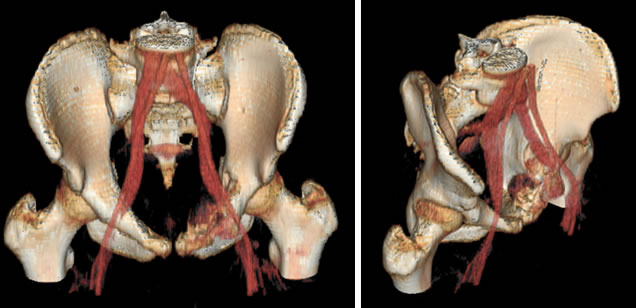

Le suddette lesioni presentano una ipervascolarizzazione patologica rifornita da uno o più vasi e sono caratterizzate dalla presenza di cavità incluse ripiene di detriti cellulari e sangue, separate da setti connettivali, sono tipici i livelli liquidi ben visibili alla TC ed alla RM.

L’embolizzazione arteriosa selettiva delle formazioni cistiche aneurismatiche, eseguita con l’utilizzo di GLUBRAN 2 (colla chirurgica) come mezzo embolizzante, blocca l’eccessivo apporto di sangue alla lesione, favorendone la guarigione. Ne consegue una ristrutturazione ossea che può essere parziale, sub-totale o totale del segmento interessato.